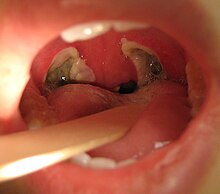

Apparence typique de l'arrière de la gorge 3 jours après une tonsillectomie